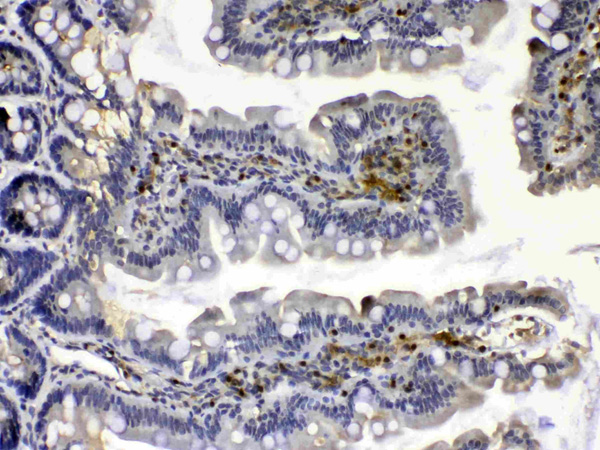

IHC (Immunohiostchemistry)

(Figure 2. IHC analysis of Calpain 2 using anti-Calpain 2 antibody (AAA124708).Calpain 2 was detected in paraffin-embedded section of human intestinal cancer tissue. Heat mediated antigen retrieval was performed in citrate buffer (pH6, epitope retrieval solution) for 20 mins. The tissue section was blocked with 10% goat serum. The tissue section was then incubated with 1ug/ml rabbit anti-Calpain 2 Antibody (AAA124708) overnight at 4 degree C. Biotinylated goat anti-rabbit IgG was used as secondary antibody and incubated for 30 minutes at 37 degree C. The tissue section was developed using Strepavidin-Biotin-Complex (SABC) with DAB as the chromogen.)